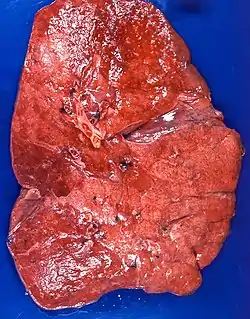

| Lipid pneumonia, exogenous Case 108 | |

The gross appearance of a lipid pneumonia is that in which there is an ill-defined, pale yellow area on the lung. This yellow appearance explains the colloquial term "golden" pneumonia.[7]

At the microscopic scale foamy macrophages and giant cells are seen in the airways, and the inflammatory response is visible in the parenchyma.